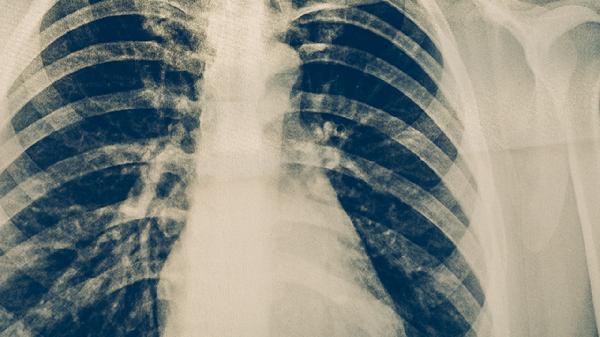

肺结核用中药一般不能单独治愈,但可作为辅助治疗手段。肺结核是由结核分枝杆菌引起的慢性传染病,规范抗结核药物治疗是核心方案,中药主要用于缓解症状或减轻药物副作用。

现代医学对肺结核的治疗以联合抗结核药物为主,如异烟肼片、利福平胶囊、吡嗪酰胺片等,需持续用药6-9个月。中药如百部、白及、丹参等虽具有滋阴润肺、止血化痰的功效,但无法有效杀灭结核杆菌。部分中药制剂如结核丸配合西药使用,可能帮助改善咳嗽、盗汗等症状,但单独使用易导致病情迁延。